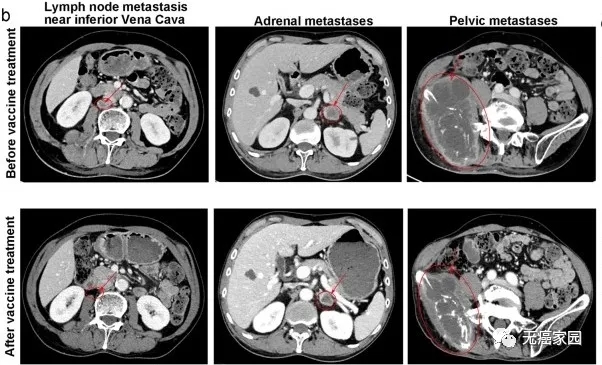

图中患者靠近下腔静脉的转移瘤基本消失,肾上腺转移及盆腔巨大转移灶明显缩小

结果显示,12名患者中,3名患者的肿瘤明显缩小,6名患者肿瘤保持稳定,疾病控制率达75%,疗效维持最长的患者已经2年。

对于复发性晚期癌症患者,这种联合疗法可以发挥抗肿瘤的作用,而且不会增加毒性及副作用。Deo-DCVac疫苗是安全和有效的,并适用于晚期肺癌患者。